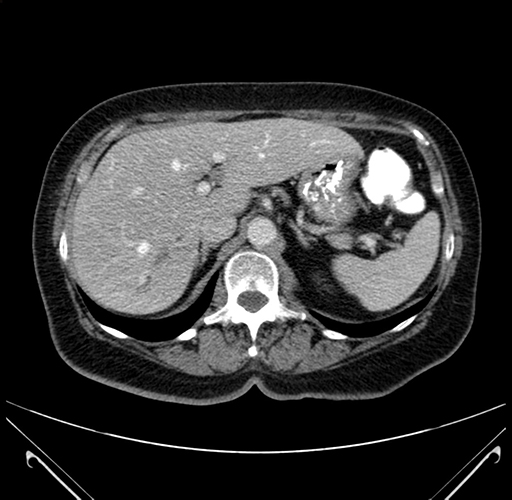

Pre-Chemo: Axial Venous

Axial Venous